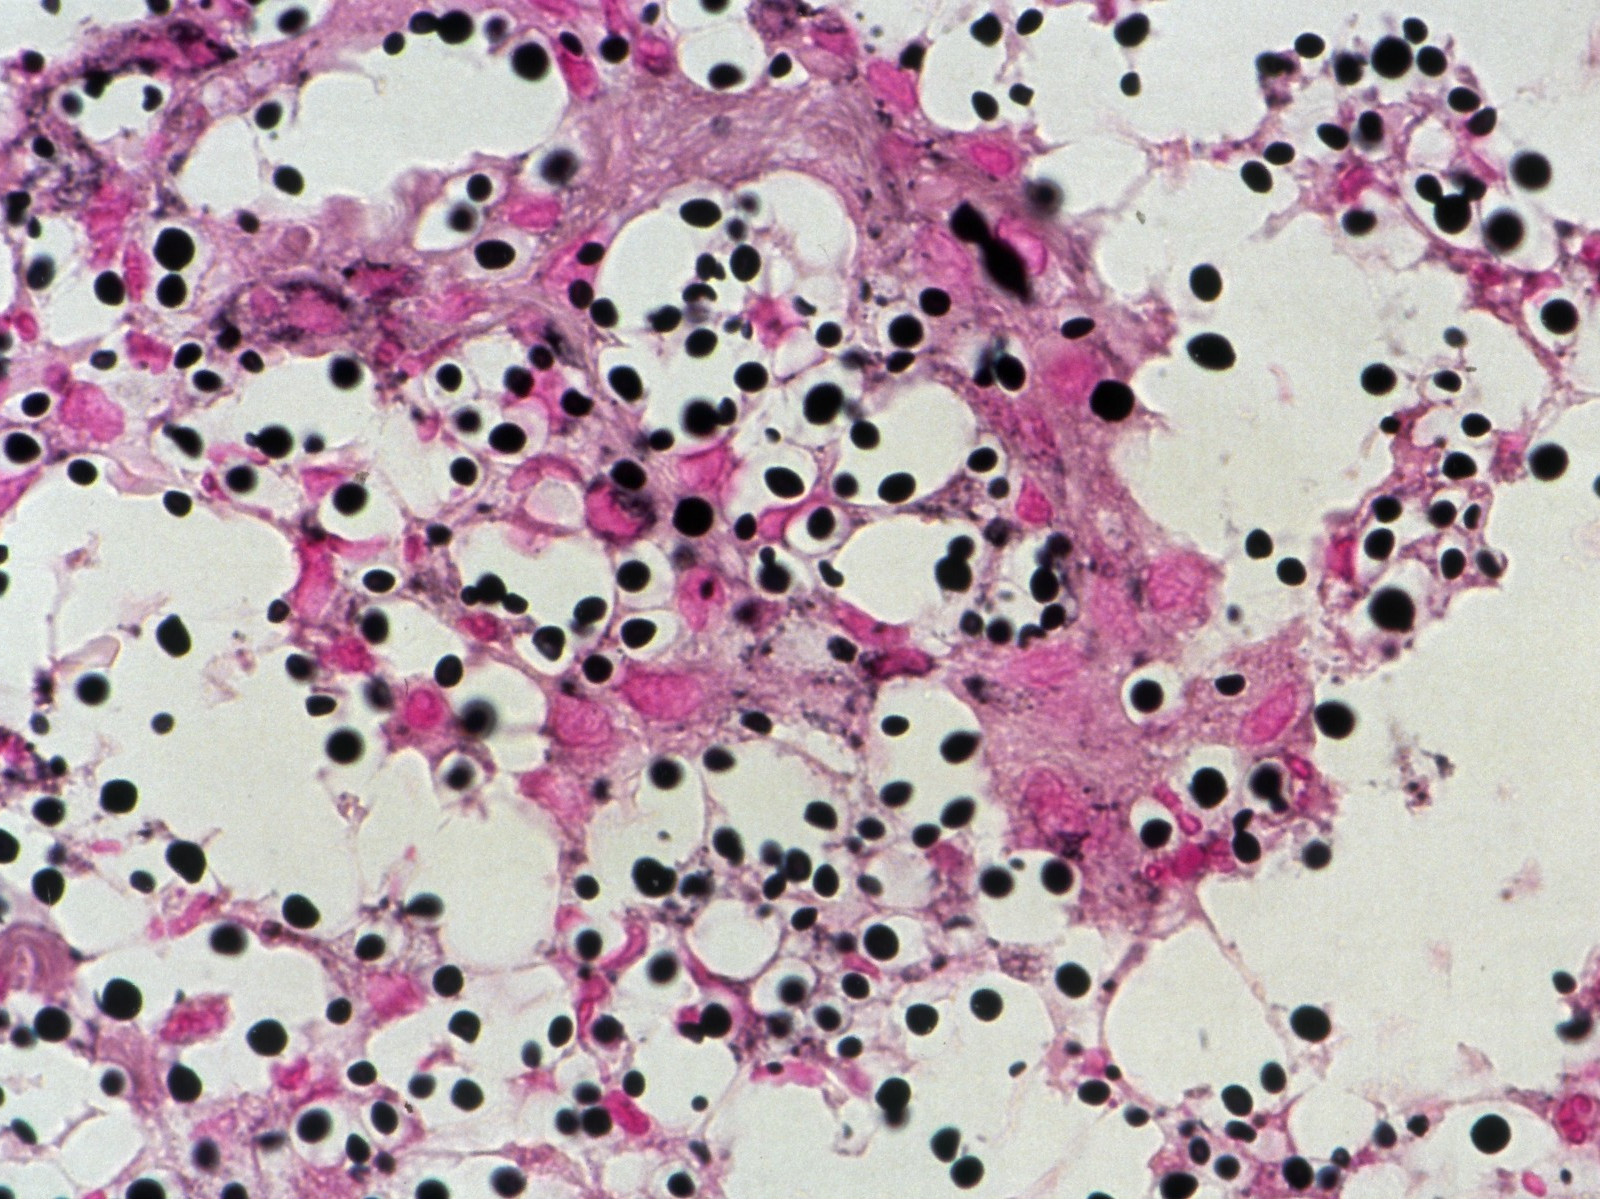

cryptococcen (PA) cryptococcen (PA) Cryptococcus neoformans

PA-foto rechtsonder: Michael Bonert (Nephron) - Wikimedia (Creative Commons License 3.0).

2 biopten van suspecte laesie, voor PA (PAS- of mucikarmijnkleuring) en kweekbiopt. Indien van toepassing aspiraat/vocht opsturen voor kweek. Eventueel pus met 10% KOH bekijken. Gelokaliseerde cutane cryptococcosis zonder systemische infectie is uiterst zeldzaam dus aanvullend onderzoek is nodig: lab (BSE, leuko's + diff, nierfunctie, glucose, alkalische fosfatase, HIV-test, CD4), X-thorax, indien afwijkend: consult longarts (BAL, Percutane longpuntie), kweken van urine (33%), bloed (10%) en sputum (10%), consult neuroloog (lumbaal punctie, directe uitstrijk liquor, glucose, eiwit, leucocyten (lymfocytose), kweek, aantonen kapsel antigeen (90%). Het cryptococcen kapsel antigeen (latex agglutinatie) kan worden bepaald in liquor, serum, en sputum. Cryptococcen antistoffen (IIF) worden gevonden bij 77-90% van de patiënten.